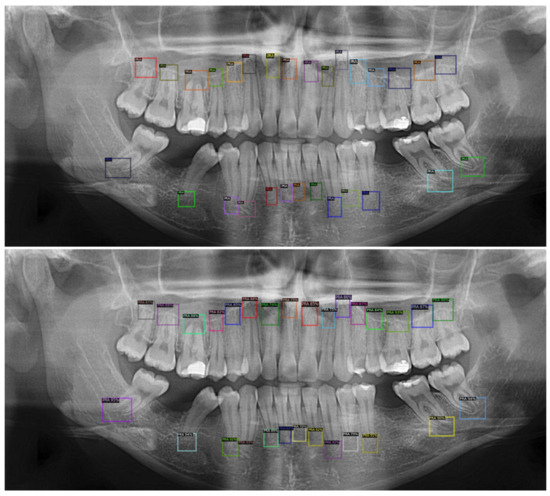

Our proposed detector identified the PRAs using a custom function based on the model aster R-RCNN. We tested two strategies to train our detector. In the first strategy (method 1) we only included unhealthy PRA (PL) for the training, while for the second strategy (method 2) we included both healthy (H) and unhealthy (PL). We trained for 1000 iterations and evaluated the detection performance of both methods based on Average Precision (AP) calculated at intersection-over-union (IOU) =0.5 on a test set of 143 images. Method 1 achieved AP50 of 38.5% while method 2 achieved AP50 of 74.95% at iteration 1000. We observed that training the detector on PRAs including H and PL classes achieved faster convergence and higher detection rates. We therefore adopted this approach in our further experiments. The proposed system then cropped and normalized all predicted bounding boxes that were then submitted to the classifier model. Figure 2 shows one example of the output of the detection model. The detector was able to adapt to the size and extension of the periapical region automatically depending on the size and extension of the roots and the lesions. This was demonstrated by the high AP50 of the algorithm. Each periapical area was labeled independently regardless of whether it was found on single rooted or multi rooted teeth.

Figure 2. Detection of periapical areas (PRA) on panoramic radiograph by clinicians and by the AI. First image: OPG showing the PRA annotated by the expert clinician. Second image: OPG showing the proposed PRA generated by the detection model for the same image. All PRAs were detected by the proposed model (Faster RCNN).